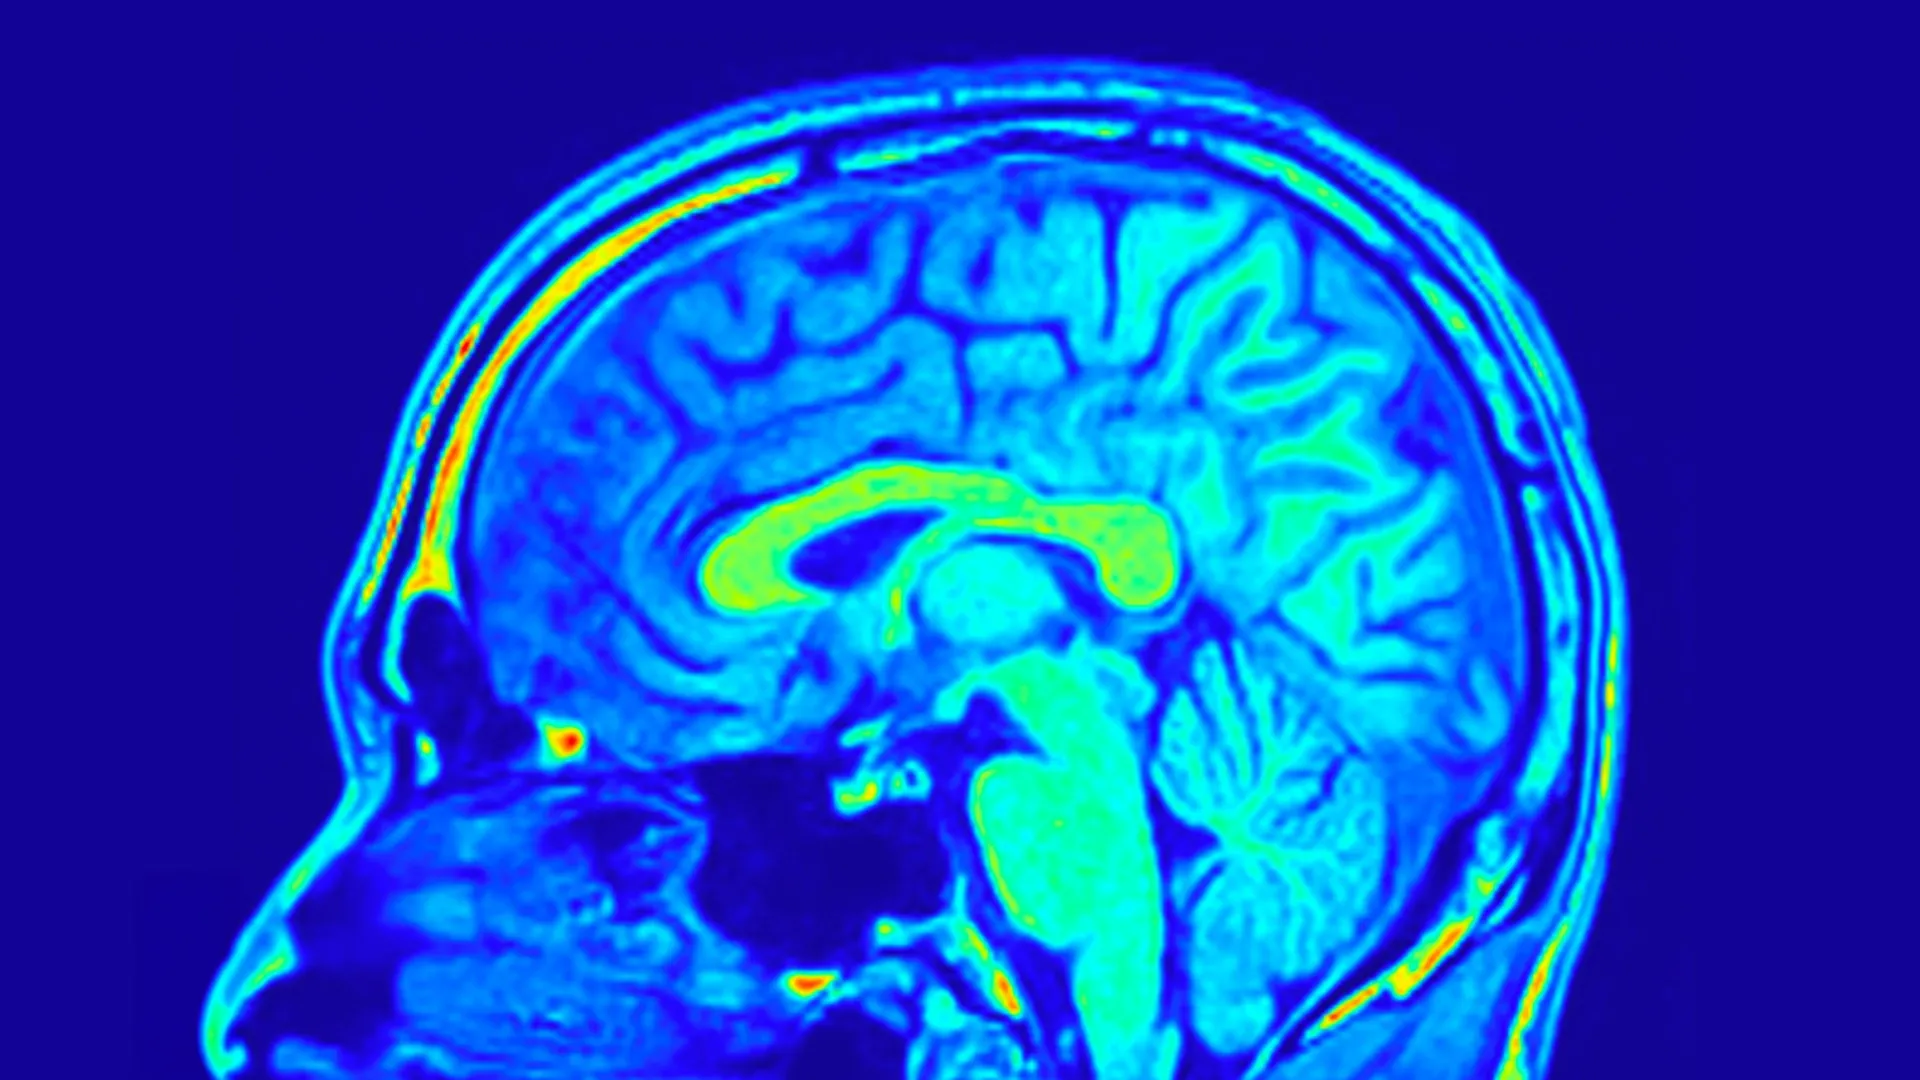

To comprehensively assess the impact of these interventions, the research team employed a multi-faceted approach to outcome measurement. The severity of depressive symptomatology was systematically quantified using the Hamilton Depression Rating Scale, specifically the 24-item version (HAMD-24), a psychometric instrument widely regarded as a gold standard in clinical depression assessment. In parallel, biological data were meticulously collected through the acquisition of peripheral blood samples, and advanced magnetic resonance imaging (MRI) scans of the brain were performed to meticulously examine alterations in both the structural architecture and the biochemical milieu of the brain.

The insights gleaned from the brain imaging data offered an even more profound understanding of the underlying neurobiological changes. The researchers identified specific interconnected networks of brain structures, termed functional brain networks, that exhibited a predictive capacity for changes in depression scores within both treatment cohorts. These networks are illustrative of the complex organizational patterns and communication pathways between disparate regions of the brain.

More remarkably, a subset of these brain network configurations proved to be predictive of treatment response exclusively in patients receiving Yueju Pill. These predictive patterns were derived from quantitative assessments of sulcus depth and cortical thickness – anatomical features that delineate the intricate folding of the cerebral cortex and the thickness of its outermost layer, respectively. Both sulcal depth and cortical thickness are intrinsically linked to fundamental aspects of brain development, structural integrity, and functional capacity. Further granular analysis revealed that the brain’s visual processing network, in particular, played a conspicuously important role in forecasting improvements in both depressive symptoms and BDNF levels among individuals undergoing treatment with Yueju Pill.

Collectively, these groundbreaking findings strongly suggest that specific brain network signatures, discernible through high-resolution MRI scans, possess the potential to serve as reliable predictors of individual patient responses to Yueju Pill therapy for MDD. This sophisticated approach represents a significant departure from traditional symptom-based diagnostic and therapeutic paradigms, heralding a new era of personalized antidepressant care.